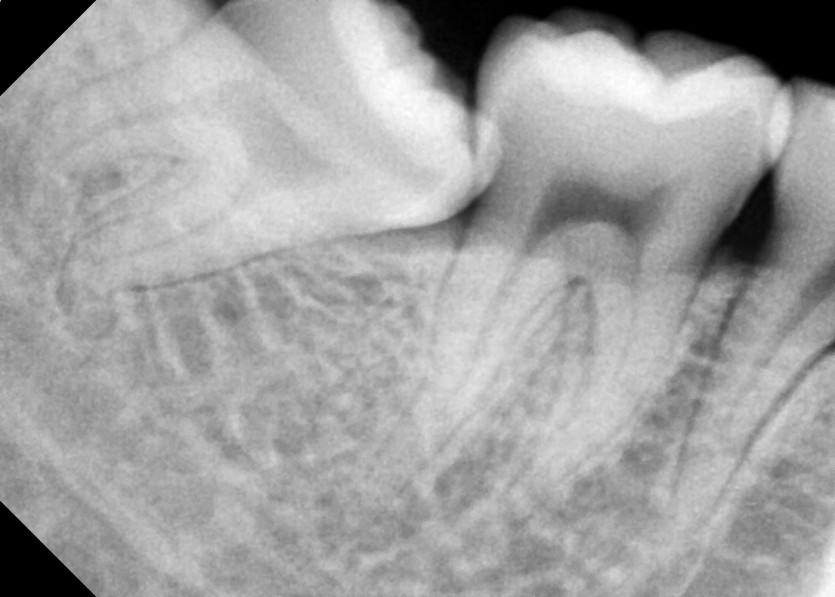

#18,48 사랑니 발치

구강 외과 전문의가 당일 발치했습니다.